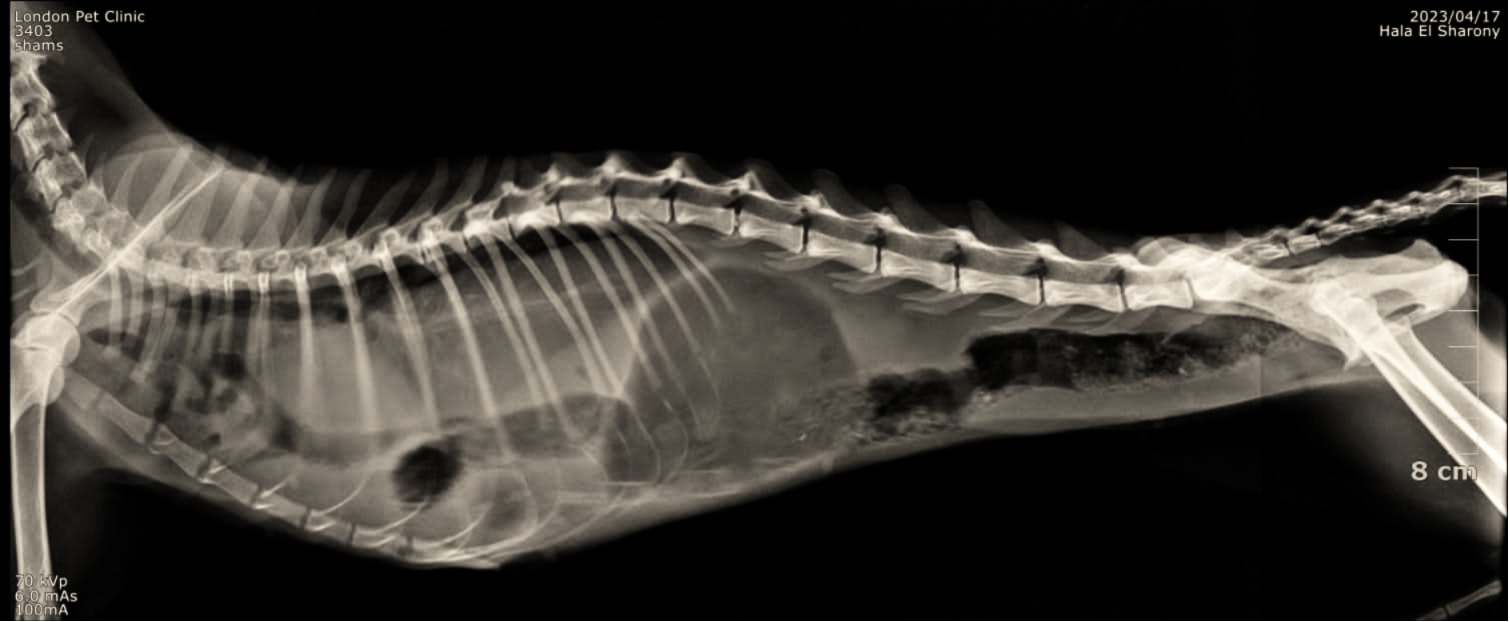

. Thoracic Radiographs

• Loss of normal diaphragmatic line

• Loops of gas-filled bowel visible within the thoracic cavity

• Heart silhouette displaced cranially

• Reduced lung fields (atelectasis)

Loss of normal diaphragmatic line Loops of gas-filled bowel visible within the thoracic cavity

intestines & Liver lobe passing through a narrow hole after being healed over